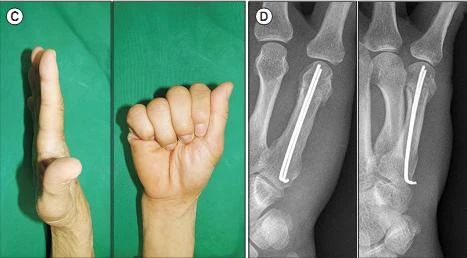

На рисунке выше показаны 4 метода внутренней фиксации спицами К. a. Ретроградная интрамедуллярная фиксация спицами К; б. Антероградная интрамедуллярная фиксация спицами К; в. Поперечная фиксация спицами К-образной формы; д. Ретроградная фиксация перекрещенной спицей К (из ссылки 9)